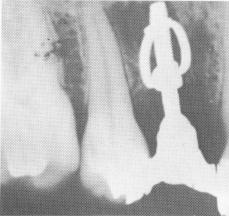

Fig. 5-14. A, Lehman's implant used successfully. Notice the bone regrowth through the band. B, Although the uppermost part of the implant is quite close to the alveolar crest, bone appears to have filled in well around the band and lower post. (From Chercheve, R.: Les implants endoosseux, Paris, 1962, Librairie Maloine.)

In addition to the cautious operative procedure necessary to create the walls of the slit, the implantologist must take great care to create a slit deep enough to set the bands well into bone. Bone can, and should, condense around the band (Fig. 5-14). This is frequently a problem. Because the post necessitates having deep alveolar bone, the implant may not be used in numerous sites because of danger to vital anatomic landmarks. Also, because the band leaves a large "empty" area within it, the danger of soft tissue invagination is great (Fig. 5-15) .